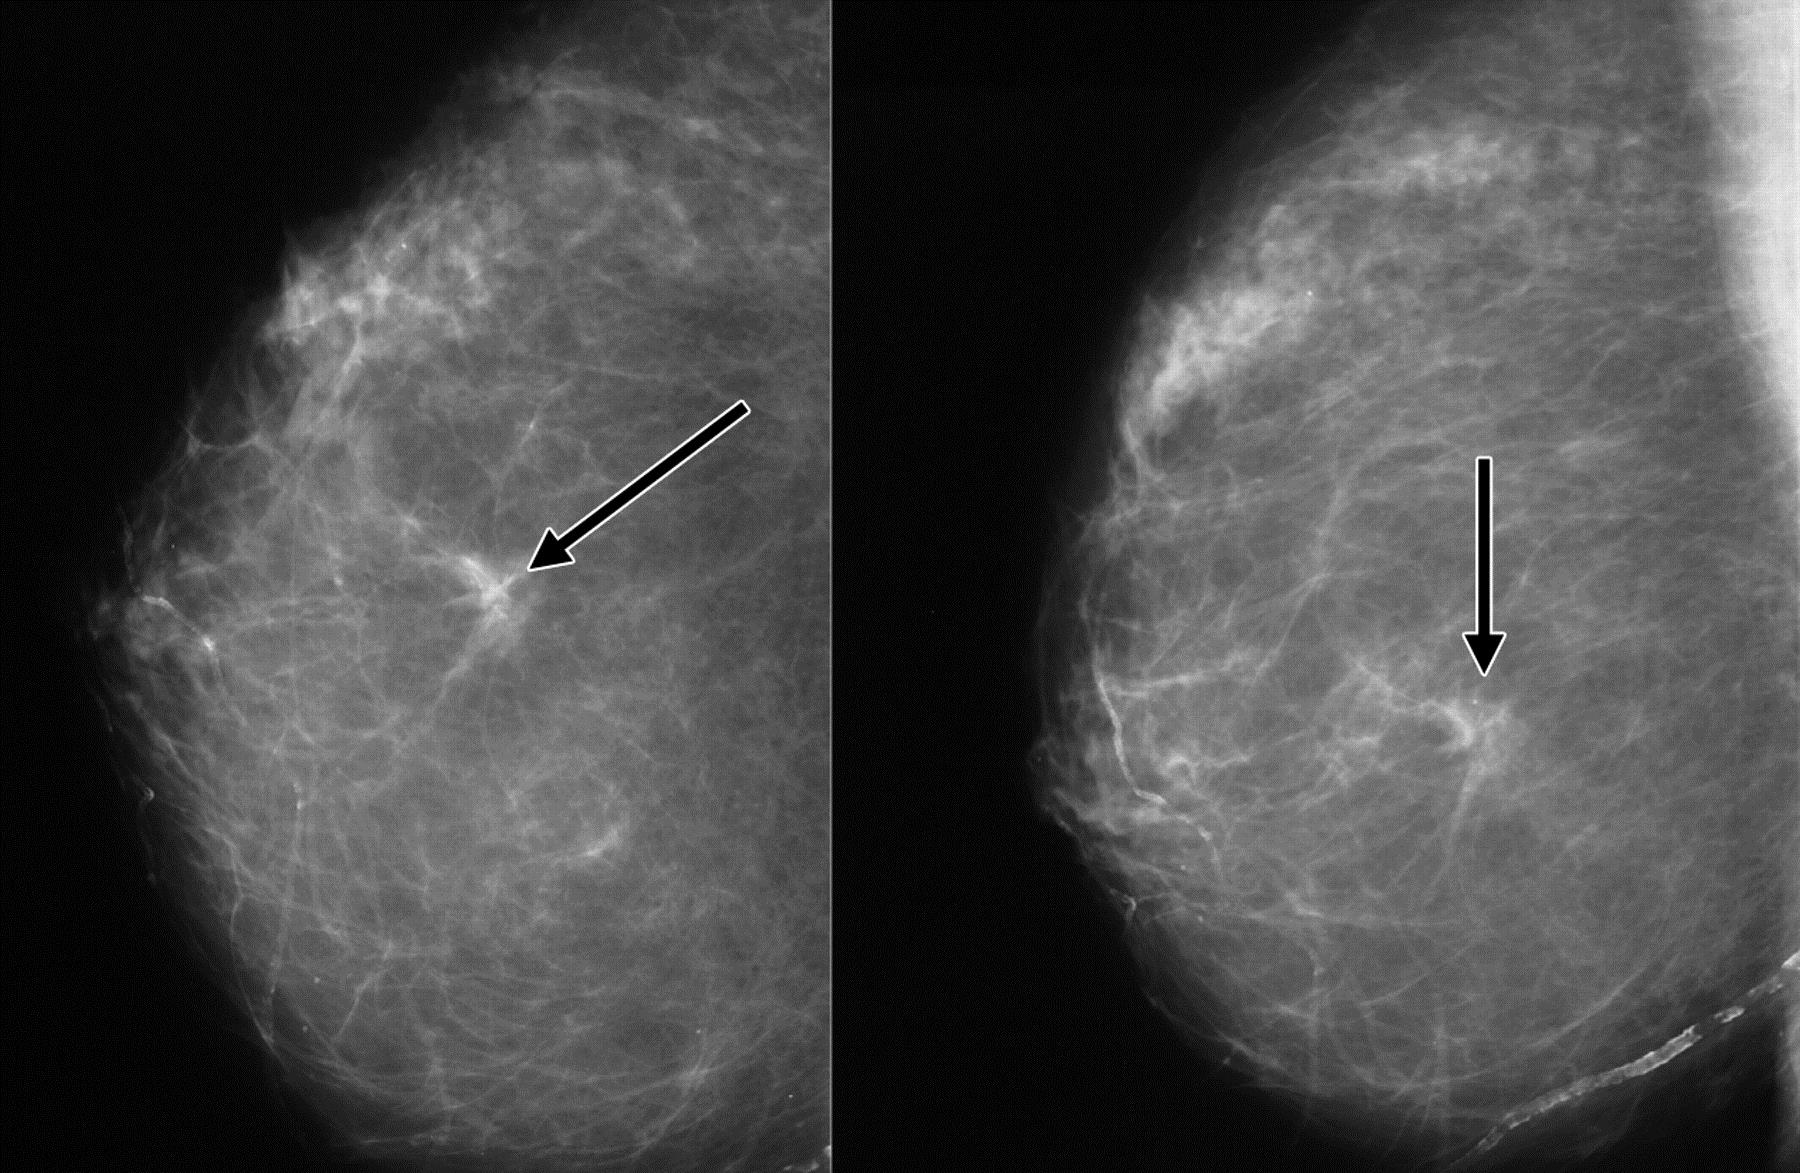

Что такое маммография: важность, процесс и результаты

Раздел: Необычные решения